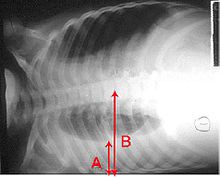

A chest radiograph is frequently used in diagnosis. In people with mild disease, imaging is needed only in those with potential complications, those who have not improved with treatment, or those in which the cause in uncertain. If a person is sufficiently sick to require hospitalization, a chest radiograph is recommended. Findings do not always correlate with the severity of a disease and do not reliably distinguish between bacterial infection and viral infection.

X-ray presentations of pneumonia may be classified as lobar pneumonia, bronchopneumonia (also known as lobular pneumonia), and interstitial pneumonia. Bacterial, community-acquired pneumonia, classically show lung consolidation of one lung segmental lobe which is known as lobar pneumonia. However, findings may vary, and other patterns are common in other types of pneumonia. Aspiration pneumonia may present with bilateral opacities primarily in the bases of the lungs and on the right side. Radiographs of viral pneumonia may appear normal, hyper-inflated, have bilateral patchy areas, or present similar to bacterial pneumonia with lobar consolidation. Radiologic findings may not be present in the early stages of the disease, especially in the presence of dehydration; or may be difficult to be interpreted in those who are obese or have a history of lung disease. A CT scan can give additional information in indeterminate cases.